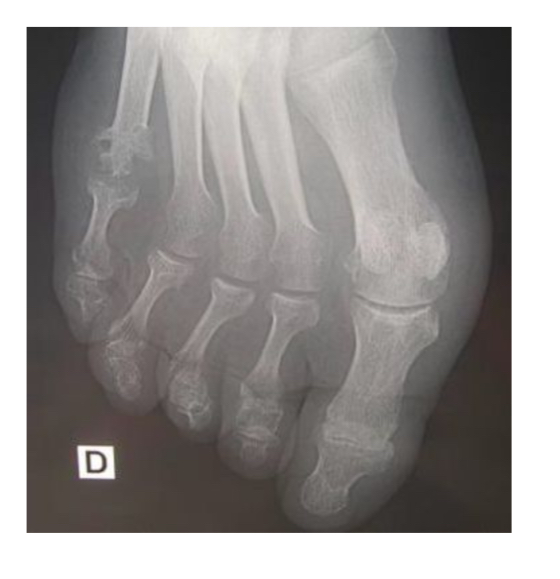

Goutte chronique

pincement global 1ere MTP

Érosions multiples

Tophus sous-cut